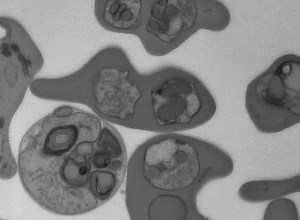

Organisms Video - Multiple Fission in Plasmodium

Class 8 - Plasmodium

Cycle - Multiple